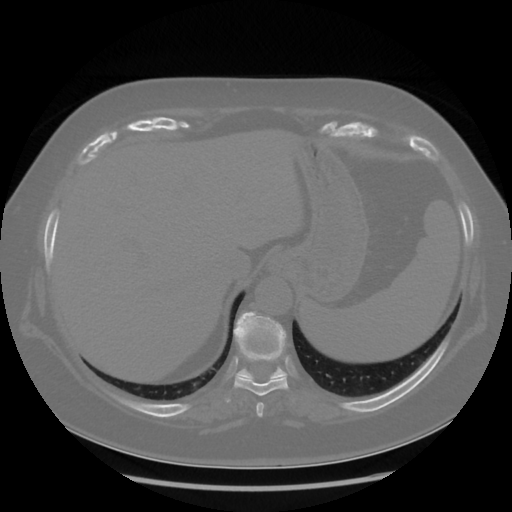

Original NATIVE CT scan (input)

Full window (WL 1023.5, WW 4095 β†’ Low βˆ’1024, High +3071)

Actual HU range: [-1024.0, 1077.0]

Lung window (WL -600, WW 1500 β†’ Low βˆ’1350, High +150)

Actual HU range: [-1350.0, 150.0]

Mediastinum window (WL 40, WW 400 β†’ Low βˆ’160, High +240)

Actual HU range: [-160.0, 240.0]